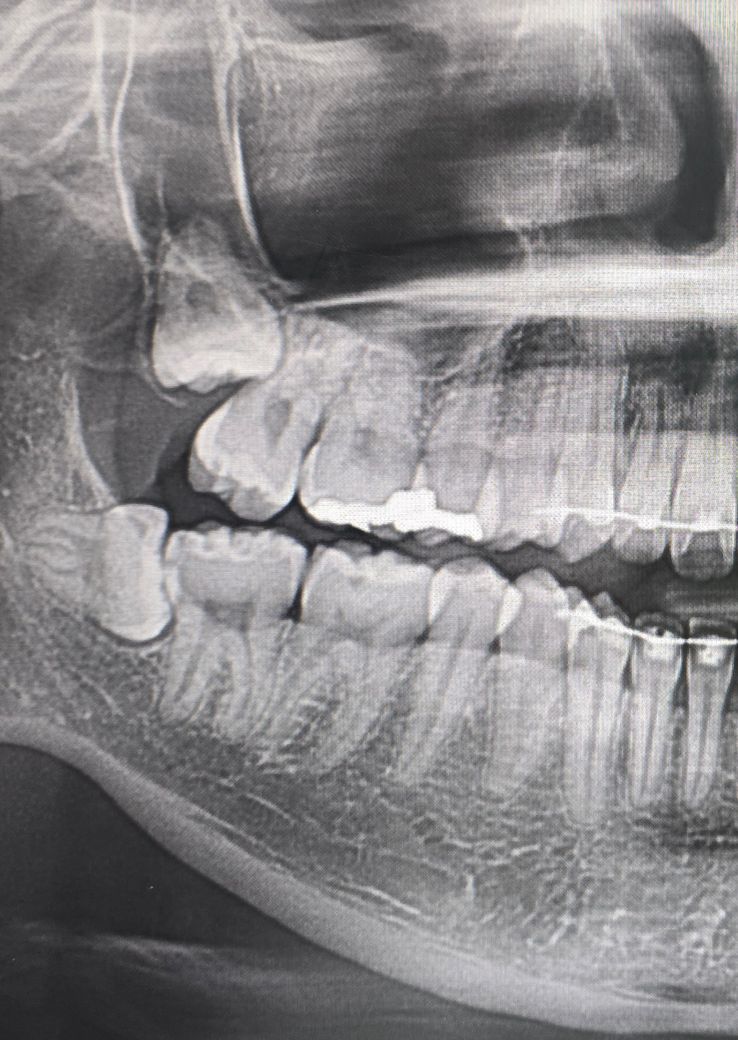

위에 사랑니 빼야되는 사랑니인가요?

위에 있는 사랑니 안빼면 옆에 어금니 썩거나 염증 뭐 그런 문제 안생기나요?

위 아래 사랑니 모두 앞으로 기울어져 있는 상태입니다. 특히 위와 아래 사랑니 의 깊이를 비교 하자면 위 사랑니가 아래 사랑니의 뿌리 보다 더 깊은 곳에 위치해서 발치 할 때 더 난이도가 높습니다.

따라서 아래 사랑니를 우선적으로 발치 하는 걸 추천 드리고 위 사랑니는 좀 더 두고 지켜 본다음에 혀로 몸을 만져 봤을 때 이전보다 더 불룩해져 있거나 치아의 머리가 뾰족하게 만져지게 되면 발치를 하면 되고 그런 일이 없다면 일년에 한번씩 치과에 가서 엑스레이를 찍어 보고 문제가 없는지 확인을 하면 좋겠습니다.

만약에 확인을 했는데 위 사랑니가 아직 나오지 않았음에도 불구하고 앞에 어금니의 뿌리를 흡수시키거나 충치가 발생해서 통증을 유발 하는 상황이 되면 무리를 해서라도 뽑는 게 좋은 상황입니다.

• 문제가 생길지 안생길지는 사실 알 수 없습니다. 엑스레이 사진도 3d가 아니기 때문에 정확한 위치 파악도 어렵습니다.

다만 빼실거면 어릴 때 빼는 게 유리합니다.

• 지금으로서는 옆 어금니에 영향을 주고 있을 확률이 높긴합니다 치아 뿌리 흡수, 치아 뿌리 부위 충치 유발의 가능성이 있습니다 발치를 하는 것이 좋을 것 같습니다

• 위에 나와 있는 사랑니의 경우에는 잇몸 안에 회복되어 있는 것으로 보입니다 특별한 문제를 일으키지 않는다면 굳이 발치할 필요는 없을 것으로 생각됩니다.

아래 있는 사랑니는 기울어져 난 상태에서 부분적으로 맹출되어 있기 때문에 해당 부위에 이물질이 끼게 되면 충치나 치료질환이 유발될 수 있습니다.

이런 경우에는 예방적으로 발치를 하는 것이 좋습니다 자세한 확인을 위해서 치과에서 진료를 받아 보는 것을 권해 드립니다.